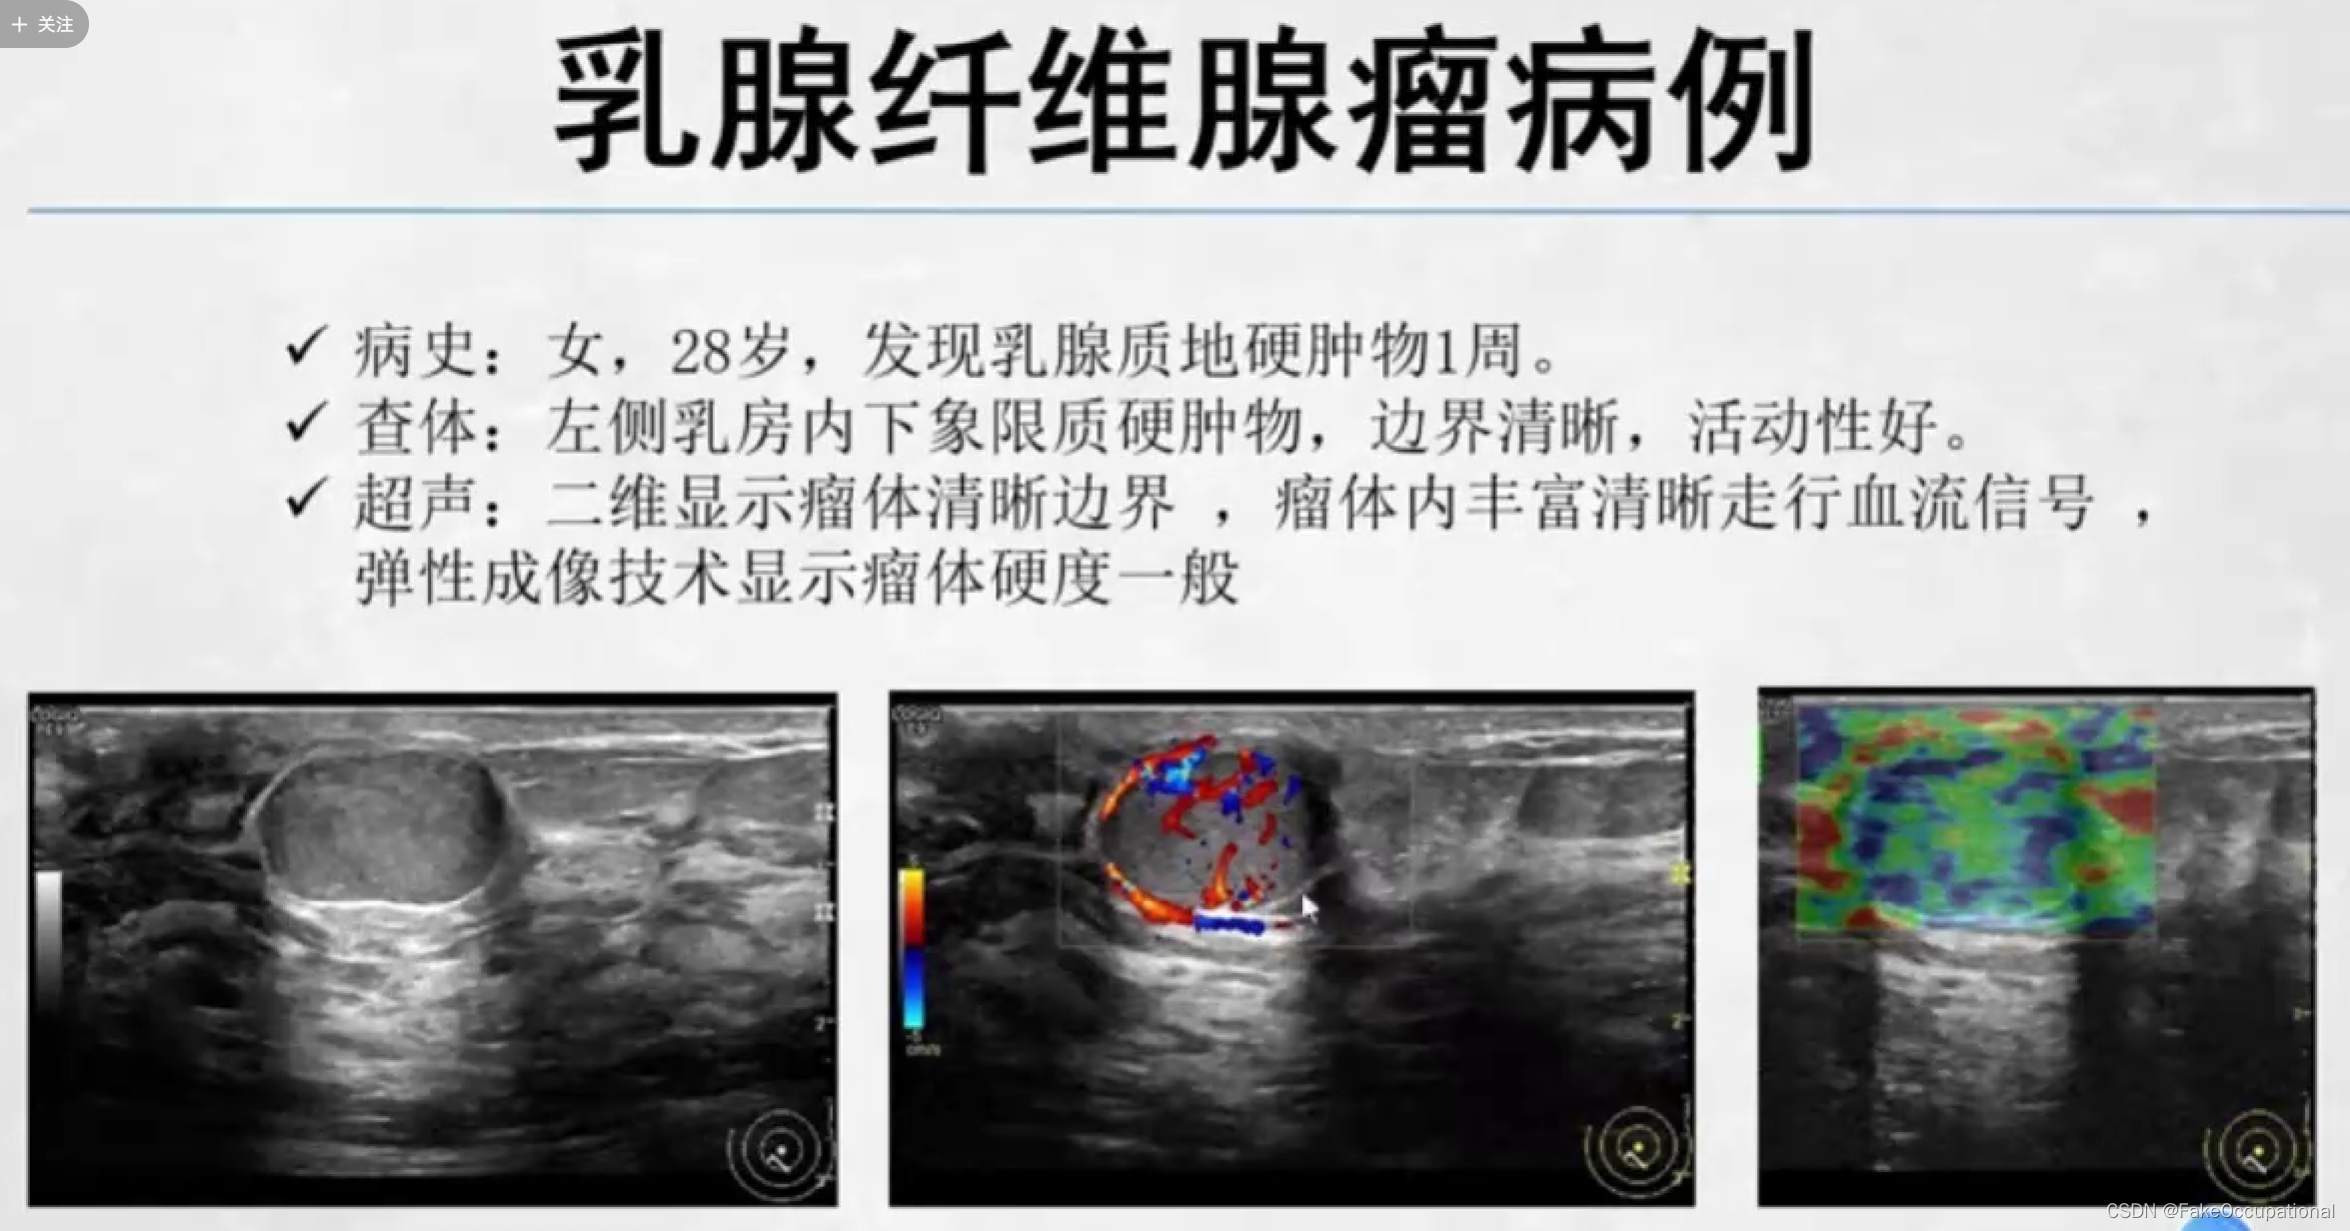

乳腺纤维腺瘤

乳腺纤维瘤 (breast fibroadenoma)

最常见的乳房良性肿瘤,约占乳腺肿瘤的10%

与女性雌激素刺激有关

常见于生育年龄的妇女,特别是30岁以下的女性

无痛、实性、边界清楚、生长缓慢的孤立性结节,触之可移动部分可在同侧或双侧、同时或不同时发生多发性结节